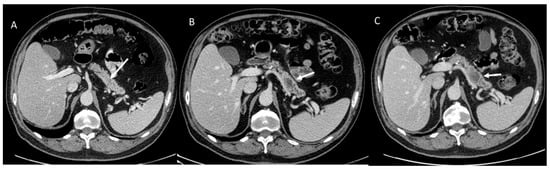

- Granata, V.; Fusco, R.; Catalano, O.; Setola, S.V.; Castelguidone, E.D.L.D.; Piccirillo, M.; Palaia, R.; Grassi, R.; Granata, F.; Izzo, F.; et al. Multidetector computer tomography in the pancreatic adenocarcinoma assessment: An update. Infect. Agents Cancer 2016, 11, 57. [Google Scholar] [CrossRef]

- Granata, V.; Grassi, R.; Fusco, R.; Galdiero, R.; Setola, S.V.; Palaia, R.; Belli, A.; Silvestro, L.; Cozzi, D.; Brunese, L.; et al. Pancreatic cancer detection and characterization: State of the art and radiomics. Eur. Rev. Med. Pharmacol. Sci. 2021, 25, 3684–3699. [Google Scholar] [CrossRef] [PubMed]